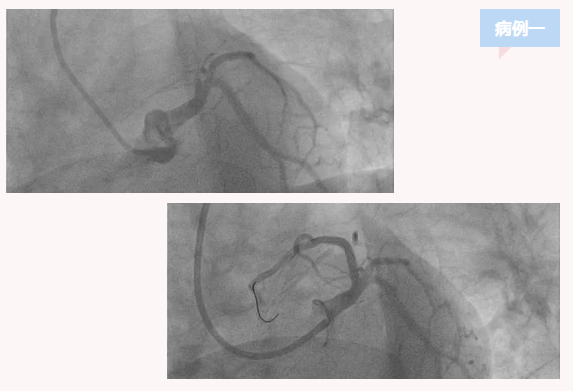

患者一,女,48岁,主因胸痛16小时来诊,急诊查心电图提示急性广泛前壁心肌梗死,急诊行介入治疗。造影提示前降支近段完全闭塞,其余冠脉基本正常,放置支架一枚,术中慢血流,心源性休克,经抢救病情仍不稳定,处于昏迷状态转重症监护室,呼吸机治疗,第二天抢救无效死亡。